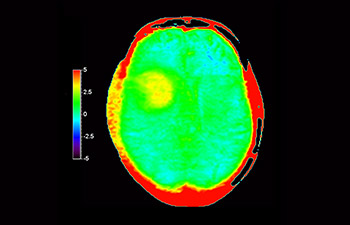

In a society where neurological disorders represent a heavy burden, Philips is committed to provide superb diagnostic clarity and treatment guidance for all patients. Today, although MR is the gold standard in neuro oncology imaging, its accuracy in tumor grading and treatment follow up assessment can be further improved. 3D APT (Amide Proton Transfer) is a unique, contrast-free, brain MR imaging method addressing the need for more confident diagnosis in neuro oncology. 3D APT uses the presence of endogenous cellular proteins, to produce an MR signal that directly correlates with cell proliferation, a marker of tumoral activity. 3D APT can support trained medical professionals in differentiating low grade from high grade gliomas and, in differentiating tumor progression from treatment effect1.

with 3D APT